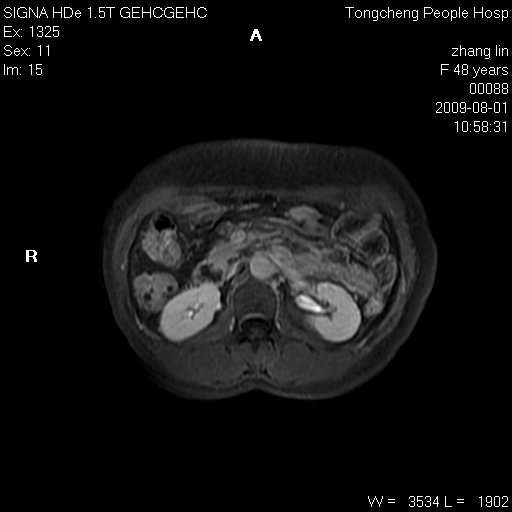

女,48岁。健康体检,彩超发现右肾占位性病变。平素健康。

临床诊断:右肾占位性病变,性质待定(囊肿?肿瘤?)。

上中腹部mr平扫+增强扫描,图像如下:

右肾上极见一类圆形病灶,t1wi呈等信号t2wi呈等高混杂信号,三期增强无强化,边界清---考虑囊肿出血。

同反相位均表现为等信号,病变无强化,考虑含蛋白的囊肿可能,弥散加权相或许有些帮助,